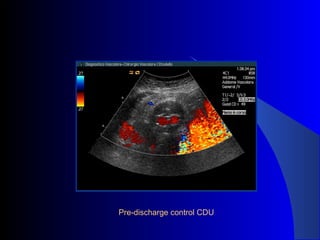

The document discusses the clinical application of the Endurant stent graft system in treating aorto-bisiliac aneurysms, detailing procedures performed on two male patients aged 72 and 73. Each patient had a history of dyslipidemia and carotid atherosclerosis, with procedures involving the bilateral bell bottom technique and the use of coils and fibrin glue. It includes pre-surgery imaging, intrasurgery angiography, and follow-up control scans to monitor outcomes.